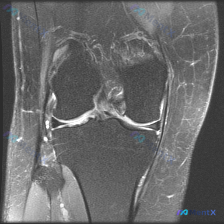

膝关节MRI阅片病例:问题问的是软骨异常,为啥我找出了半月板撕裂?

刚整理了一个有意思的膝关节MRI读片病例,原问题是让观察图像里的软骨异常,我仔细梳理了一下,分享给大家一起看看。

这是一张膝关节MRI冠状位T2压脂序列,高信号代表液体或水肿,我们直接按结构读片:

- 半月板:外侧半月板(图像左侧)可见明显贯穿性高信号,已经延伸到关节面,肯定是有损伤了;内侧半月板形态完整,信号均匀,没看到明显撕裂。

- 韧带软组织:外侧副韧带区域和周围软组织都有明显高信号水肿,半月板周围软组织也有水肿;内侧结构没看到明显异常。

- 关节腔:膝关节腔内有中等量液体高信号,符合关节积液表现。

- 骨骼肌肉:股骨远端、胫骨近端骨髓没有明显片状高信号,排除明显骨挫伤;关节面平整,骨皮质连续,没有骨折;周围肌肉也没看到异常信号。

刚看到问题说找「软骨异常」,第一反应是找关节面的透明软骨病变,但仔细看了一圈,这张片子上股骨和胫骨的关节面透明软骨没有看到明确的信号异常、缺损或者变薄,反而外侧半月板的异常非常明显。

- 外侧半月板贯穿性高信号到关节面——这是半月板撕裂的典型MRI表现

- 外侧副韧带+周围软组织水肿——提示外侧结构有急性损伤反应

- 关节中等量积液——继发性炎症反应,符合急性损伤表现

- 阴性线索:没有骨挫伤、没有骨折、没有透明软骨异常、没有骨侵蚀或占位

综合下来,最符合影像表现的结论是:急性创伤导致的外侧半月板撕裂,合并外侧副韧带复合体损伤,继发性膝关节积液,本张影像没有看到明确的关节透明软骨异常。